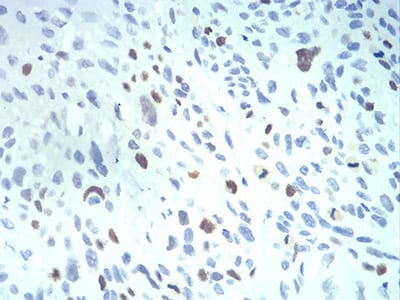

Immunohistochemical analysis of paraffin-embedded human esophageal cancer tissues using KPNA2 mouse mAb with DAB staining.